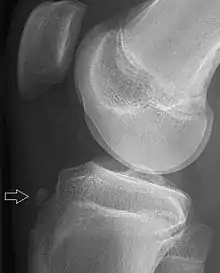

| Avulsion fracture | |

| Avulsion fracture of a fingertip bone | |